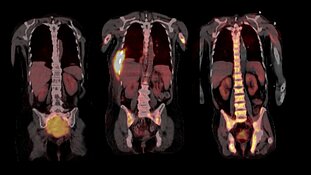

Ihre Arbeit basiert auf Proben aus dem weltweit größten Myelom-Zentrum an der University of Arkansas for Medical Sciences in Little Rock (USA), wo beide Wissenschaftler mehrere Jahre lang gemeinsam geforscht haben. Im Jahr 2017 hatten sie bereits in Nature Communications über die räumliche, genomische Heterogenität der Tumorzellen berichtet. „Bis vor kurzem wurden in der Forschung immer nur einzelne Knochenmarkproben aus dem Becken untersucht. Ein erwachsener Mensch verfügt jedoch über etwa fünf Kilogramm Knochenmark, die sich über das gesamte Skelettsystem verteilen. Somit ließ sich die Evolution der Tumorzellen bislang gar nicht ausreichend abbilden," schildert Privatdozent Dr. Leo Rasche, Erstautor der Studie und Juniorgruppenleiter am Mildred-Scheel-Nachwuchszentrum (MSNZ) für Krebsforschung am Uniklinikum Würzburg die Ausgangslage. Die Forscher und ihre Teams haben nun 140 Proben analysiert, die in einem Zeitraum von bis zu 13 Jahren aus verschiedenen Skelettlokalisationen von 24 Myelom-Patientinnen und -Patienten gewonnen wurden. Dazu wurden zum Teil bildgebende Verfahren wie Magnetresonanztomografie (MRT) und Positronen-Emissions-Tomografie (PET) genutzt, um die Tumorherde, die so genannten fokalen Läsionen abzubilden.

Fokale Läsionen sind die Hotspots der Tumor-Evolution

Durch die Nutzung der bildgebenden Verfahren kamen die Wissenschaftler zur ersten wichtigsten Erkenntnis: Dass die entscheidenden Schritte der Tumor-Evolution oft außerhalb des Beckens, in den Tumorherden ablaufen. „In den fokalen Läsionen haben wir Mutationen gefunden, die wir sonst nirgendwo gesehen haben und die aggressiver erschienen, da sie in die Kategorie der so genannten Cancer Driver Genes - genetische Veränderungen, die das Krebswachstum ankurbeln - fielen. Die Eigenschaften der Tumorzellen können sich jedoch nach jeder Therapie-Linie unterscheiden, sogar dann, wenn sich die Tumormasse während der Therapie nicht verändert hat. Wir schließen daraus, dass regelmäßige biologische Untersuchungen des Myeloms während der Therapie erfolgen müssen, wenn die Erkrankung gezielt behandelt werden soll", resümiert Niels Weinhold, Leiter der Translationalen Myelom-Forschung am Universitätsklinikum Heidelberg.

Generell sei bei allen Behandlungen, auch nach vermeintlich erfolgreicher Therapie eine regelmäßige Untersuchung vonnöten. „Wir bitten unsere Patientinnen und Patienten auch in der Remission alle drei Monate zu uns, um eine Kontrolle im Blut durchzuführen und gegebenenfalls mittels MRT oder PET zu prüfen, ob es fokale Läsionen gibt", schildert Leo Rasche. Unbehandelt versterben die Betroffenen in der Regel innerhalb eines Jahres.